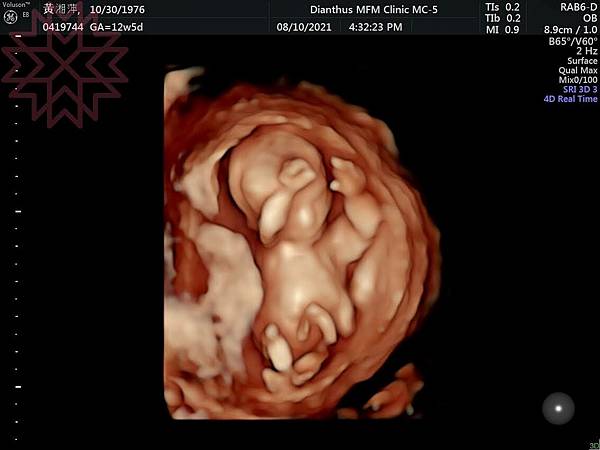

話從懷孕 27-28 週開始。上方照片是懷孕約 12 週時泡泡的高層次超音波,後來就沒有這麼清晰形體的影像了⋯XDKirororo 發表在 痞客邦 留言(0) 人氣(321)